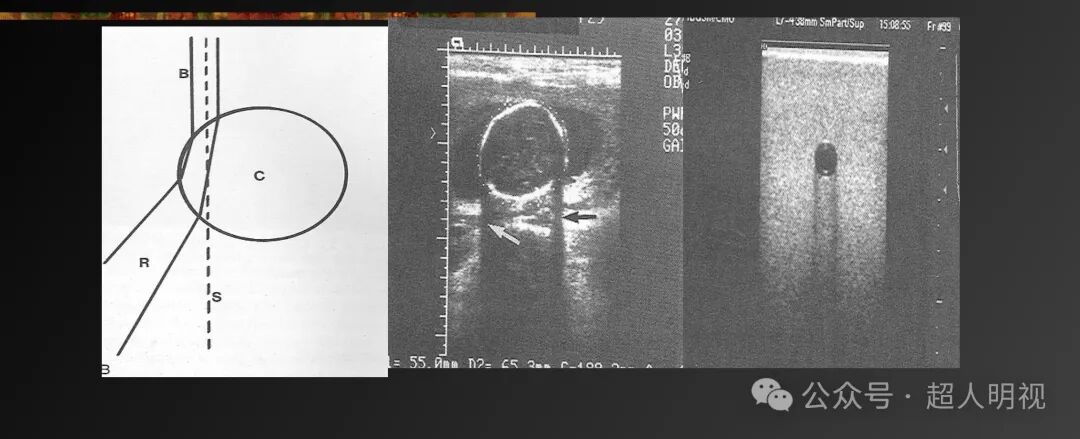

- 边缘声影(弯曲界面处的声束偏折和折射导致衰减)

彩超伪像是什么超声伪像_https://www.jmylbn.com_新闻资讯_第4张